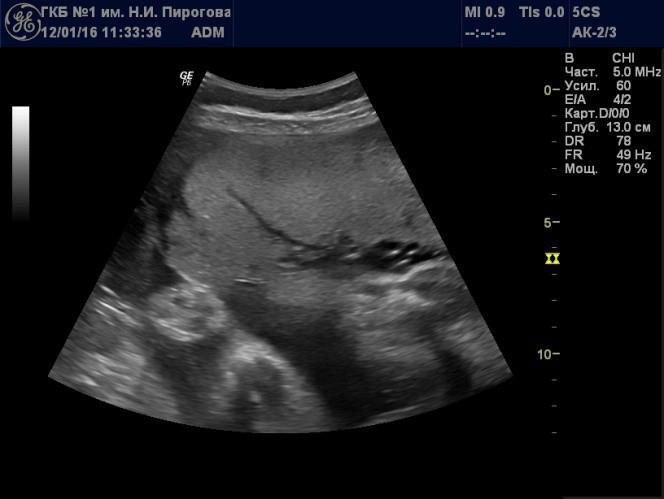

В свою очередь, эхогенность хориальной пластинки будет зависеть от угла сканирования. Наиболее высокой эхогенностью будут отличаться участки, отразившие УЗ волну под углом 90º (Рис. 6).

Рис. 6. Беременность 30 нед. Хориальная пластинка части плаценты, расположенной по передней стенке матки, при прямом (а) и косом (б) углах сканирования.